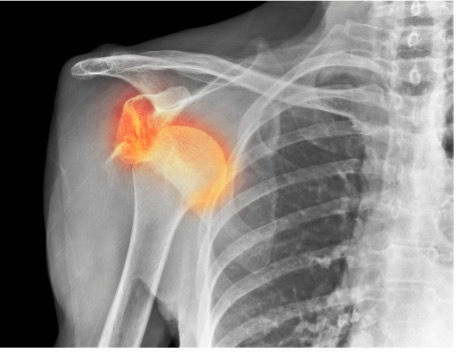

肩脱臼はラグビーや柔道などのコンタクトスポーツ に多く見られる疾患です。ではなぜ?コンタクトスポーツに多く見られるのでしょう?

それは地面に体を打ち付けたり、肩の脱臼が生じやすい体勢を強制されることが多く、肩の構造の許容範囲を超えた外力が加わることが原因です。よって肩の脱臼は外傷による受傷がそのほとんどです。